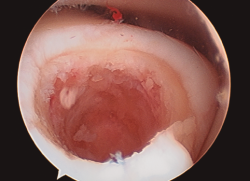

Figura 2. Técnica de estimulación medular con nanofracturas. Obsérvense los bordes del curetaje y la cruentación de la capa mineralizada.

- Posteriormente, realizamos la técnica de estimulación seleccionada entre: brocado o microperforaciones o nanoperforaciones. Preferimos realizar estas últimas a perforaciones más grandes que pueden dañar el hueso subcondral u otras técnicas de brocado con agujas de Kirschner que pueden producir necrosis inducida por el efecto térmico (Figura 2). Cada “nanofractura” debe realizarse separada 3-4 mm con una profundidad de 9-10 mm y un diámetro de 1 mm.